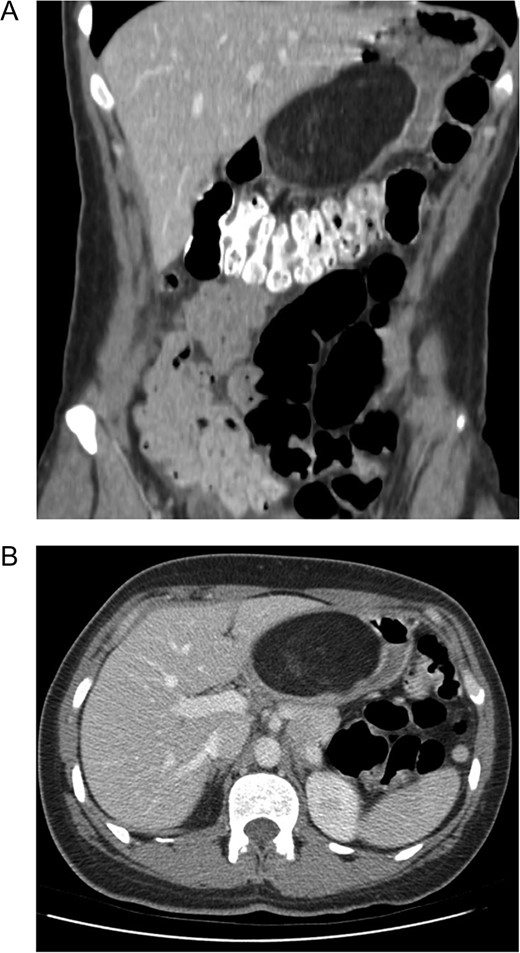

A 39-year-old female presented to her primary care physician with ~1 year of upper GI bleeding. She was a recent Ukrainian immigrant and had not undergone previous evaluation. She was referred to a gastroenterologist and underwent upper endoscopy with mucosal biopsy of a large antral mass. She declined endoscopic ultrasound (EUS) and was briefly lost to follow up over the course of a pregnancy. She returned to seek care for ongoing anemia and new epigastric pain. Esophagogastroduodenoscopy (EGD) with EUS was performed identifying a 6 cm mass within the muscularis propria of the antrum. Based on these findings, she was referred to a surgeon and underwent pre-operative computed tomography (CT) of the abdomen and pelvis which demonstrated a 9.7 × 7.8 × 4.8 cm3, heterogeneous mass with internal septa adherent to the posterior wall of the gastric antrum (Figs 1 and 2).

Computer tomography demonstrating a large (9.7 × 7.8 × 4.8 cm3) mural based mass extending along the posterior wall of the lesser curve of the stomach, effacing the lumen. (A) Coronal. (B) Axial. The mass contains predominantly fat signal with areas of hazy internal enhancement. No pathological lymphadenopathy was noted.